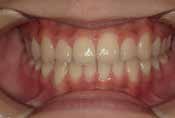

出っ歯

他院で「抜歯して5年かかる」と言われましたが、非抜歯、1年で治りました

Sさん (矯正開始時:12歳)

Before

After

下の奥歯が内側に傾いて、舌の位置が悪く、鼻がつまって口呼吸の状態でした。扁桃腺がよく腫れ、風邪をひきやすく、いびきもあるようでした。

治療を終えて

装置で上あごを拡大し、下の歯の位置を整え、前歯の並びを整えました。お口のトレーニングの効果で鼻詰まりと、いびきも改善。たった1年でこの変化が見られました。もちろん歯は1本も抜いていません。

主訴・治療内容 他院にて「抜歯した上で、ワイヤーを付け、5年かけて治療する」と言われ、他の方法はないのかとネットで調べたところ、当院を知り無料相談に来院されました。

治療期間 1年

費用 462,000円(税込)